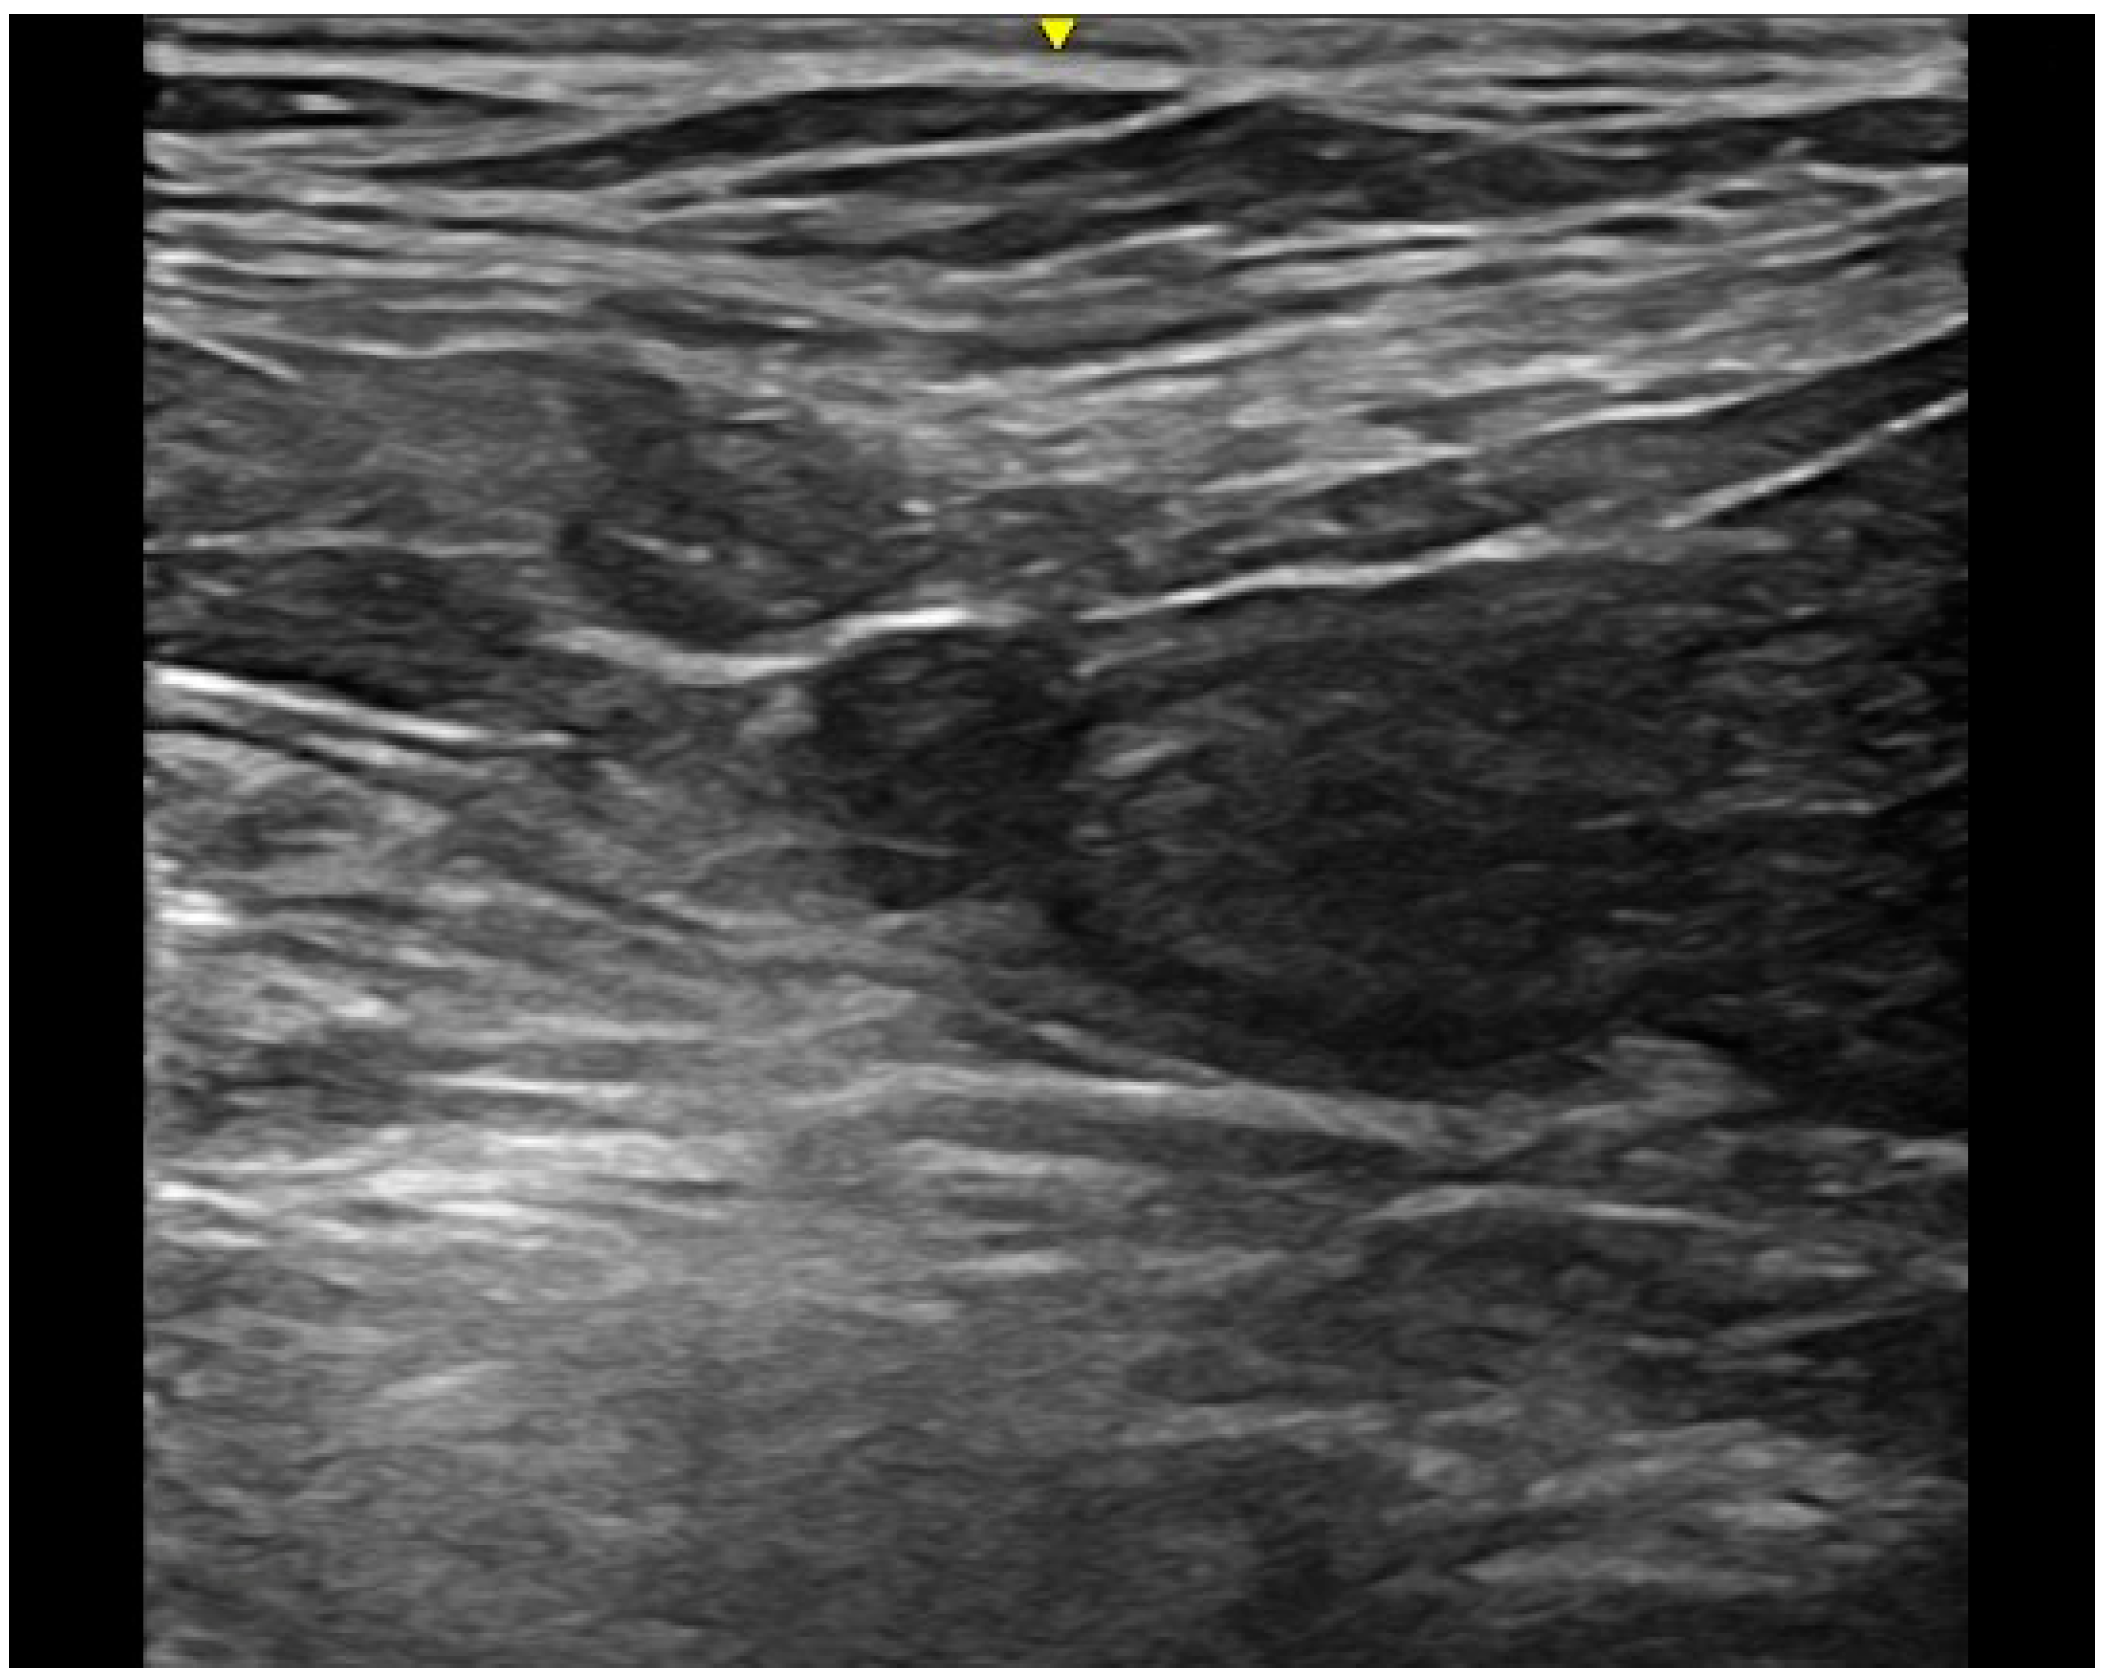

Historically, the diagnosis of UA in veterinary medicine was performed by the use of different imaging techniques, such as ultrasonography, contrast cystography, and cystoscopy [3,14,23]. In previous studies, contrast cystography was used to diagnose UA [8,12]. According to Osborne and colleagues, positive antegrade cystourethrography and retrograde positive contrast urethrocystography were considered the procedures of choice for the diagnosis of vesicourachal diverticula [4]. In the present study the diagnosis of UA was based on abdominal ultrasonography only. Abdominal ultrasound has the advantages to be a routinely available and non-invasive imaging technique. Similarly, in human medicine, abdominal ultrasound is considered a fast and readily available technique to diagnose UA in absence of the risks connected to radiation exposure [7]. However, we should consider that the diagnostic power of abdominal ultrasonography in identifying UA may be reduced by a condition of inadequate bladder filling. In one of the patients of our study, the diagnosis of intramural vesicourachal diverticulum was made at the second ultrasonography, when the bladder appeared less filled (Figure 7). Therefore, we cannot exclude that small diverticula may be undiagnosed by the use of ultrasonography, in case of inadequate bladder filling.

Figure 7. Two longitudinal ultrasound images of the urinary bladder of a dog with an intramural vesicourachal diverticulum. The images show two different volumes of urine into the bladder lumen. (a) Overly distended: the diverticulum appears as a not very visible focal depression in the cranial-ventral aspect of the bladder, with thinning of the correspondent bladder wall; (b) ddequately distended: the diverticulum appears as an evident, focal, evagination in the cranio-ventral aspect of the bladder.